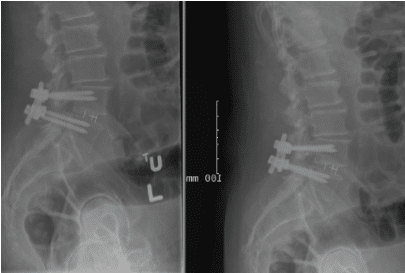

Patient underwent decompression laminectomy with decompression of nerve roots and transforaminal interbody fusion using PEEK (polyether ether ketone) cage and pedicle screw and rod fixation for fusion at L4-5 level.

Fusion was achieved in about 3 months and patient was asymptomatic.